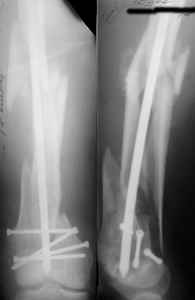

THX, initial images are

1,

2.

At that moment we had in stock only the 10 mm solid nails so of course there was no idea about early weight bearing. But it was quite enough for early knee ROM excersises (see attached). Two locking screws through the distal block provided that.